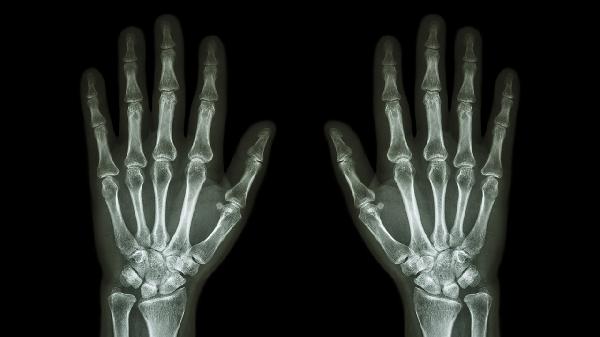

骨感染病常见哪些疾病

骨感染病常见的疾病包括骨髓炎、化脓性关节炎和结核性骨炎。这些疾病通常由细菌、真菌或其他病原体感染引起,可能导致骨骼疼痛、肿胀、发热等症状,严重时甚至影响骨骼功能。

骨髓炎是骨感染病中最常见的一种,主要由金黄色葡萄球菌等细菌感染引起。感染途径包括血液传播、外伤或手术感染。患者常表现为局部疼痛、红肿、发热,严重时可能出现脓肿或骨骼坏死。化脓性关节炎则是关节腔内感染,常见于膝关节和髋关节,症状包括关节肿胀、疼痛、活动受限,严重时可能导致关节功能丧失。结核性骨炎由结核分枝杆菌引起,多见于脊柱和长骨,症状包括慢性疼痛、局部肿胀、低热和体重下降,严重时可能导致骨骼畸形或瘫痪。